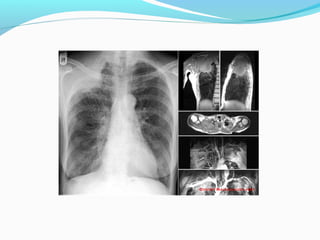

TNM STAGING

(T)

T1 - tumor

Diameter of 3 cm or smaller and surrounded by lung

or visceral pleura or

endobronchial tumor distal to the lobar bronchus

T2 - tumor

Greater than 3 and smaller than 7 cm

Invasion of the visceral pleura

Atelectasis or obstructive pneumopathy involving less

than the whole lung

Tumor involving the main bronchus 2 cm or more

distal to the carina.

T3 - tumor

Tumor with atelectasis or obstructive pneumonitis of the

entire lung

Tumor in the main bronchus within 2 cm of the carina but

not invading it

Tumor of any size with invasion of non-vital structures

such as the chest wall, mediastinal pleura, diaphragm,

pericardium.

Separate tumour nodules in the same lobe as the primary

tumor.

T4 - tumor

Invasion of vital mediastinal structures: fat, heart, trachea,

esophagus, great vessels, recurrent laryngeal nerve, carina.

Invasion of vertebral body.

Malignant pleural or pericardial effusion (cytologically

proven).

Separate tumour nodule(s) in a different ipsilateral lobe to

that of the primary tumor.